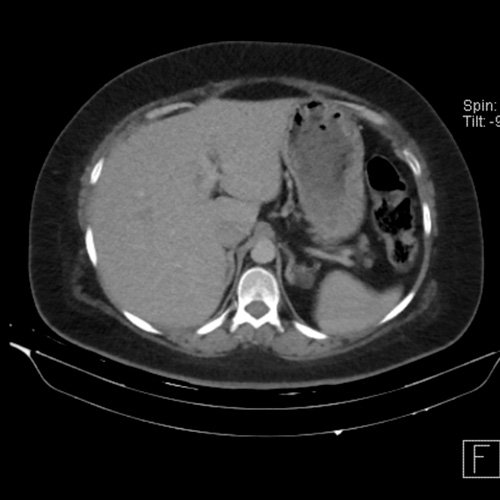

Tomografía de abdomen y pelvis sin contraste oral con contraste EV (12/02/26): El hígado es de forma, tamaño y situación habituales. Su superficie es lisa, y sus bordes son agudos. Imagen hipovascular aislada de 15 mm en segmento V de aspecto inespecífico. Sugiero complementar con RMI. La vía biliar intra y extrahepática es de calibre conservado. La vesícula biliar es de forma, tamaño y situación normales, sin imágenes que sugieran la presencia de litiasis. Tener en cuenta que este método puede pasar por alto litiasis colesterínicas. El bazo es de forma, tamaño y situación normales. El páncreas es de características normales. El conducto de Wirsung es de calibre conservado. Adenoma adrenal izquierdo de 16 mm. Ambos riñones son de forma, tamaño y situación habituales. Concentran y eliminan adecuadamente la sustancia de contraste. Sin evidencia de alteraciones calicopiélicas ni ureterales. La aorta, las arterias ilíacas primitivas, internas, externas y femorales, son de calibre y trayecto conservado, permeables. La vena cava inferior y las venas ilíacas primitivas, internas, externas y femorales son de calibre y trayectoria conservados, permeables. No se observan adenomegalias intraperitoneales, retroperitoneales, ilíacas ni inguinales. No se observan alteraciones a nivel del tracto gastrointestinal. La vejiga es de paredes lisas, sin presentar efectos de masa endoluminales ni parietales. Utero en AVF, lateralizado a izquierda. Pequeña hernia umbilical de contenido graso y escaso líquido intrasacro. No se identifican alteraciones en las estructuras óseas visualizadas.

TC de abdomen y pelvis con contraste endovenoso (12/02/2026) Corte axial: hígado de forma, tamaño y situación habituales, con superficie lisa y bordes agudos. Imagen hipovascular aislada de 15 mm en segmento V de aspecto inespecífico.

TC de abdomen y pelvis con contraste endovenoso (12/02/2026) Corte coronal: hígado de forma, tamaño y situación habituales, con superficie lisa y bordes agudos. Imagen hipovascular aislada de 15 mm en segmento V de aspecto inespecífico.

TC de abdomen y pelvis con contraste endovenoso (12/02/2026) Corte sagital: hígado de forma, tamaño y situación habituales, con superficie lisa y bordes agudos. Imagen hipovascular aislada de 15 mm en segmento V de aspecto inespecífico.